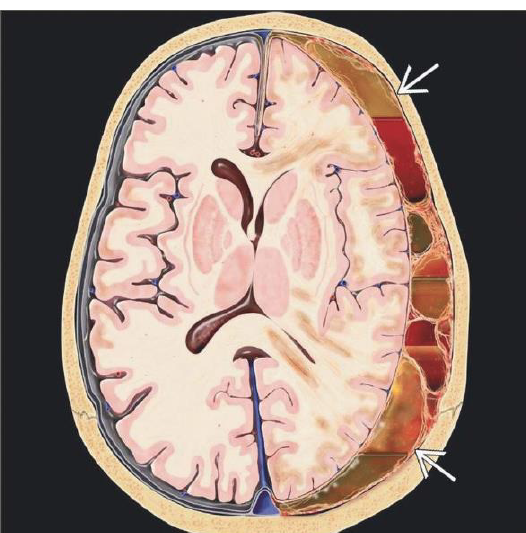

What is your dx?

Graphic depicts crescent-shaped acute SDH with contusions and “contre-coup” injuries , diffuse axonal injuries

What structures have been affected in this pt with SDH?

Acute SDH spreads over left hemisphere , along tentorium , into interhemispheric fissure but does not cross midline.